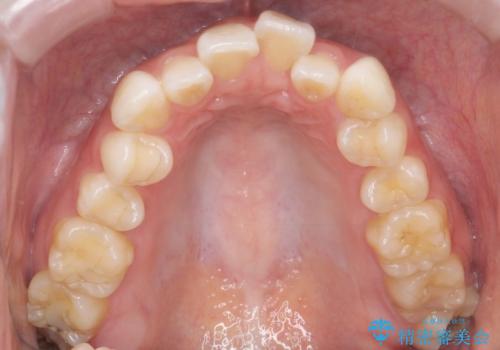

【審美装置】前歯のがたがたを治したい

- 前歯の凸凹と口元の突出感を主訴に来院されました。

臼歯関係が上顎前突傾向のため、上の小臼歯を抜歯してワイヤー矯正を行なっております。

下顎の叢生はIPRを行なって配列しています。